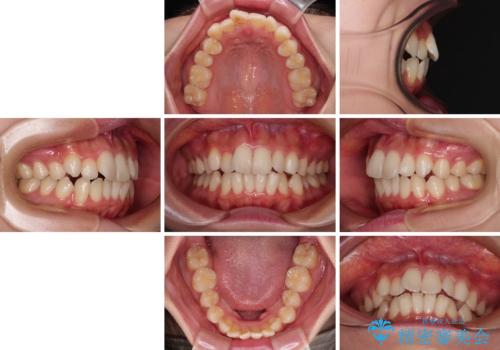

- 口元の突出感と口の閉じにくさを気にして来院された患者様です。

上下左右第一小臼歯4本を抜歯し、ワイヤー装置にて口元を引っ込めるよう矯正治療を行うこととしました。

口元の突出感が改善されてことで、下唇に引っかかっていた上顎前歯も気にならなくなりました。